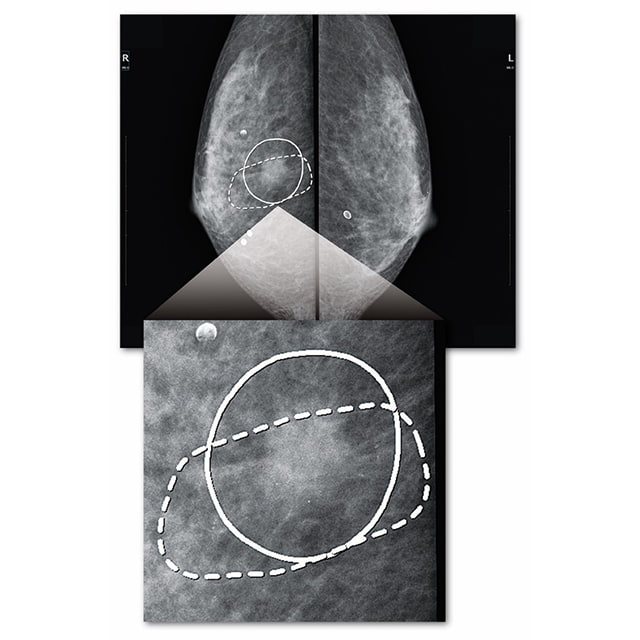

読影に優しいマーキング表示

簡単なボタン操作で、CADが検出したエリアを見やすい線で囲み表示し、画像の観察にともなうストレスの大幅な軽減に貢献します。